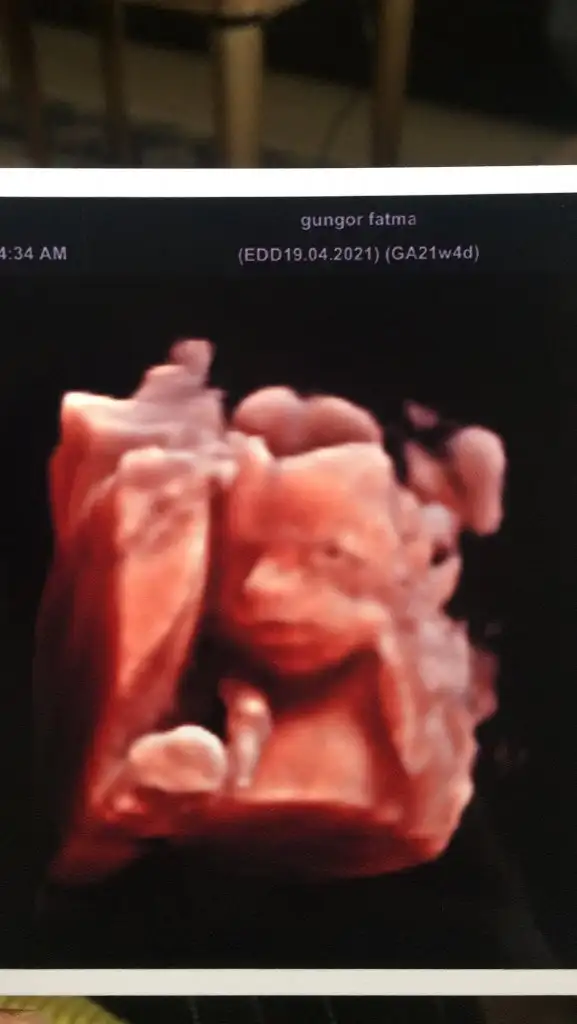

Selam herkese. Bizim de bugün kontrolümüz vardı 25+2 deyiz 800 gram olmuş oğluş boyunu sordum onu bilemeyiz dedi doktor 🤔 bu hafta içi de gidip şeker yükleme testi yaptırıcam zayıfsın ama zayıflarda da çıkabiliyor şeker o yüzden yaptır dedi dr. Güzel bir haftasonu olsun 🥰 fotoğrafımızı da ekleyeyim 😇